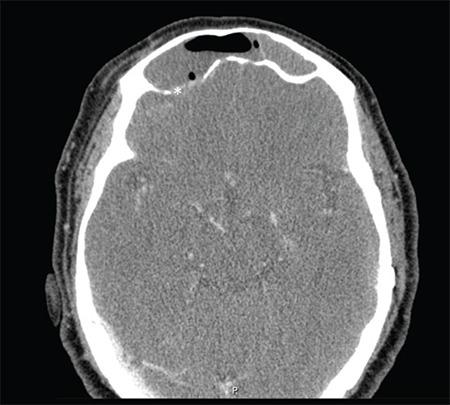

Frontal sinus keratoma or cholesteatoma is a rare disease of paranasal sinuses and presents as a slow-growing mass that becomes symptomatic as it grows to the surrounding structures. Intracranial complications are not a common presentation and are potentially life-threatening. Frequently the final diagnosis is only made intraoperatively because several other frontal sinus tumors behave likewise. Definitive treatment requires complete removal of the keratoma, and a combined endoscopic and external frontal sinus approach is a good treatment option. In this report, we presented a 68-year-old female with frontal sinus cholesteatoma with diagnostic and therapeutic features of this pathology with the review of the literature.